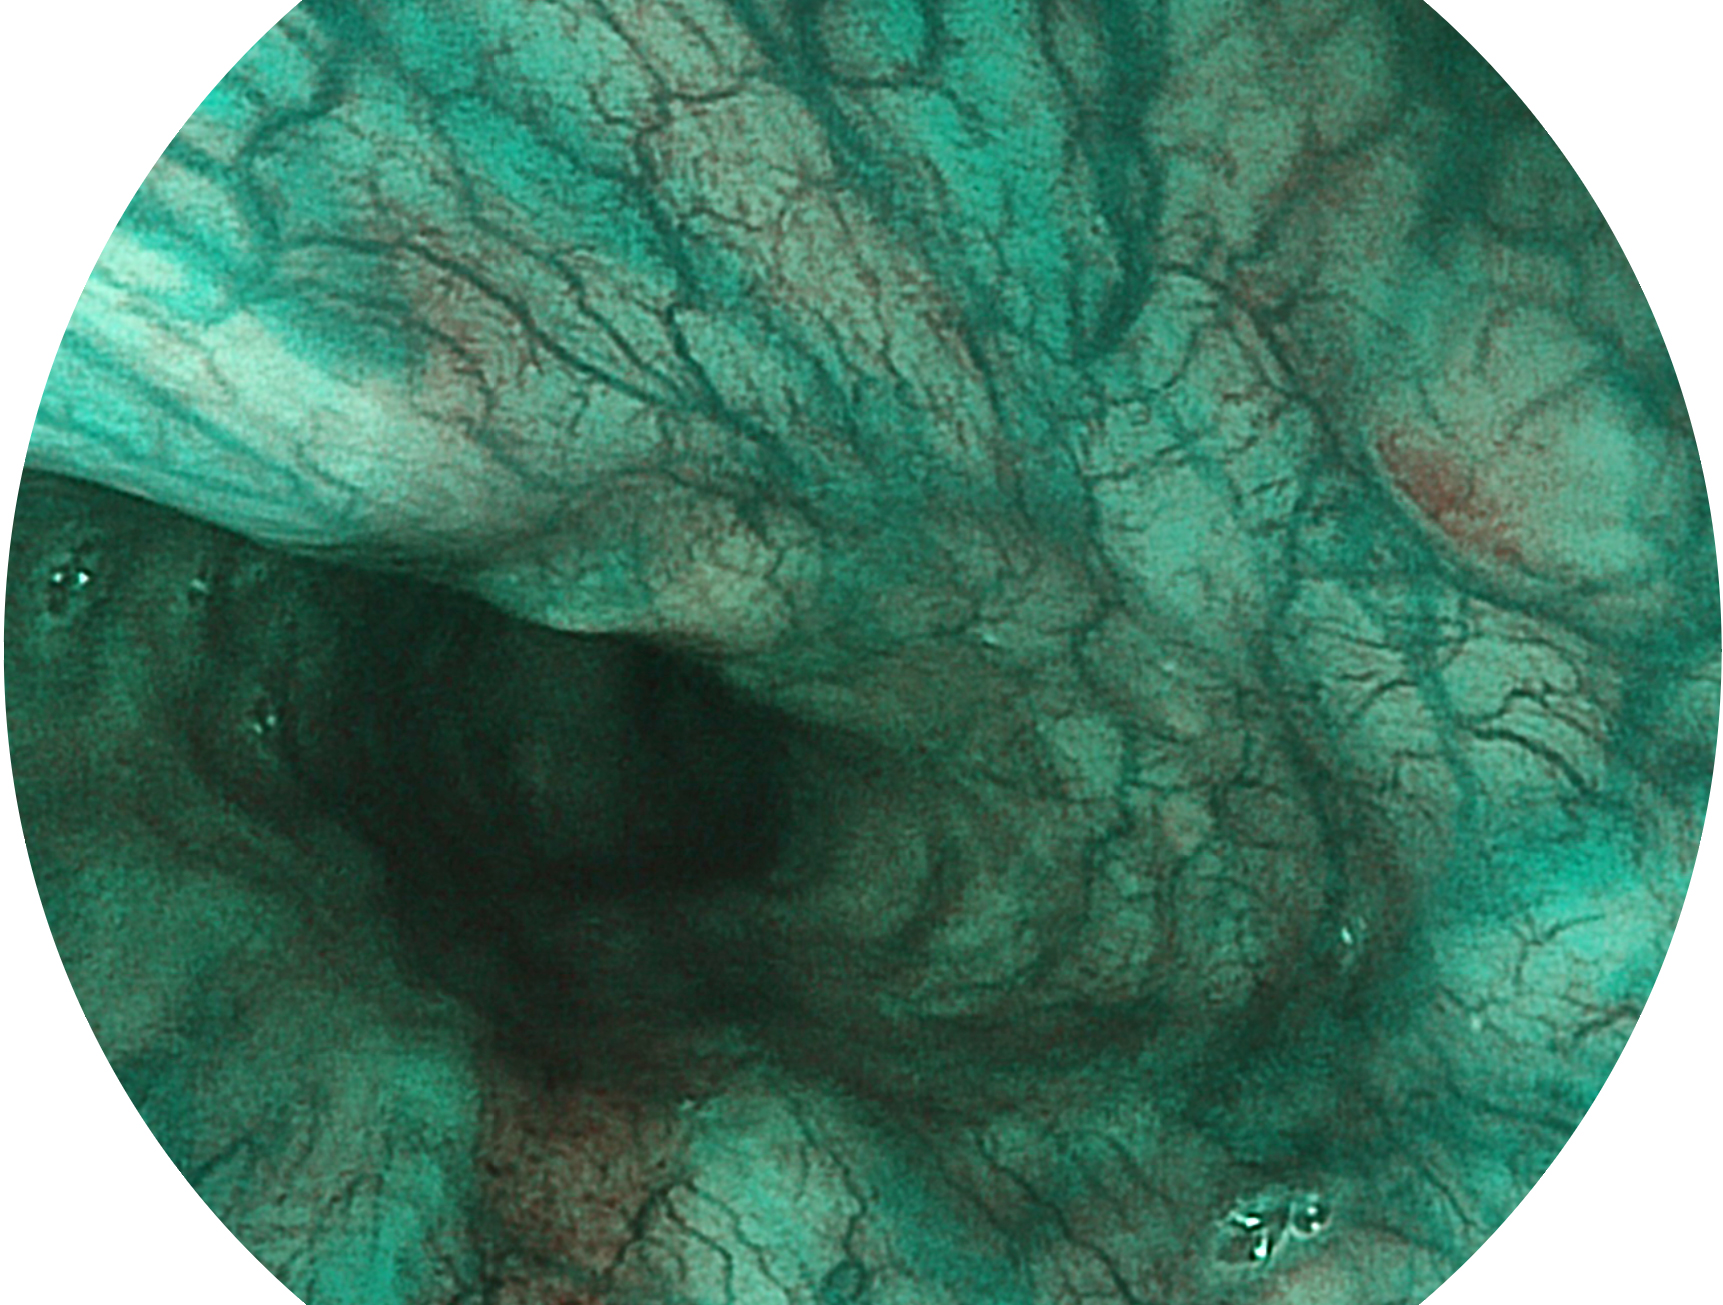

银河集团官网新开发的内镜染色技术,主要是基于多波长LED 光源的开发,VLS-55Q 四波长LED 光源是由四个不同颜色的LED光按照相应照明模式所规定的特定发光比例进行合束后形成,合束后形成的照明光的光谱由红光、绿光、蓝光及蓝紫光这四个不同的波段范围构成。具有更高光谱自由度,通过光谱比例的控制,实现了聚谱成像技术,英文全称为“Spectral Focused Imaging, SFI”,缩写为“SFI”和光电复合染色成像技术,英文全称为“Versatile Intelligent Staining Technology, VIST”,缩写为“VIST”。